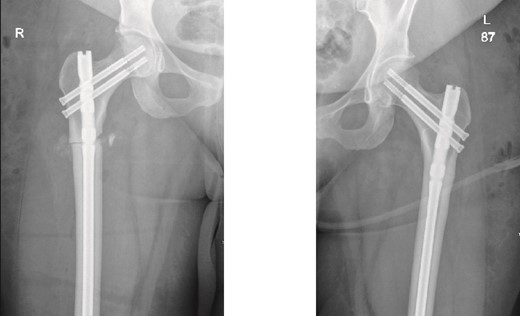

The left side was then prepped and draped. The same procedure was performed, with the nail size changed to 9 mm x 360 mm. Two proximal recon screws (90 mm) were inserted, followed by two distal screws. After fixation, the wound was irrigated, and closure was completed using Vicryl sutures for the subcutaneous tissue. The skin was closed with clips, and a sterile dressing was applied. The patient was extubated and transferred to her bed in stable condition, then moved to the post anesthesia care unit in stable condition. Immediate post-operative X-rays of both the right and left femurs are shown in Fig. 2.

Anteroposterior (AP) view of the right and left femurs after CRIF with IM nail.